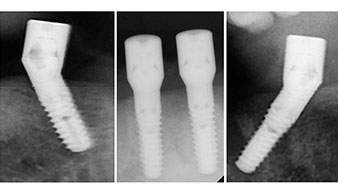

Para la planificación y la minimización del riesgo, se realizó una tomografía volumétrica tridimensional (TVD, Planmeca) que mostró que la calidad y la cantidad del tejido óseo era suficiente para la intervención quirúrgica y el tratamiento inmediato con el método Fast & Fixed. Siguiendo el protocolo de este método, se insertaron los implantes en la región de las piezas 35, 32, 42 y 45. Debido a la inclinación de hasta 45 grados de los implantes distales, el perfil de emergencia se desplazó hacia posterior y se generó un mayor polígono de soporte (fig. 3).

Este valor se corresponde con la posición siguiente del ajuste predefinido en Implantmed. Aquí se aprecia la inclinación de aproximadamente 45 grados del contra-ángulo de W&H hacia medio caudal en la región de la pieza 45 para preservar el nervus mentalis. El foramen mentale sirve como orientación anatómica para todas las perforaciones en esta zona. Las perforaciones siguientes se realizaron con una velocidad reducida de 300/rpm (figs. 10 y 11).

Tanto el contra-ángulo como la pieza de mano S-11 de W&H disponen de refrigeración externa, lo que supone una ventaja, ya que la solución de NaCl llega exactamente al lugar preciso y, en caso necesario, también puede reajustarse. Los contra-ángulos y las piezas de mano pueden desmontarse, lo que resulta muy recomendable desde el punto de vista higiénico y de la capacidad de esterilización. Se implantaron cuatro implantes SKY de 4,0 x 14 mm. Los contra-ángulos y las piezas de mano pueden desmontarse, lo que resulta muy recomendable desde el punto de vista de la higiene y de la capacidad de esterilización. Se implantaron cuatro implantes SKY de 4,0 x 14 mm.